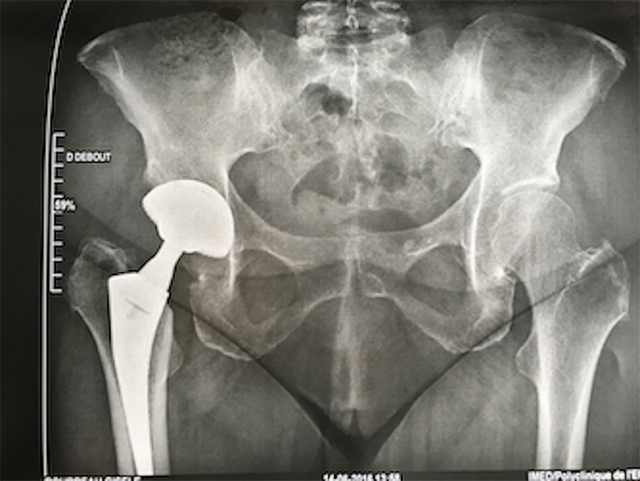

Hemiarthroplasty –үеийг хагас солих

Хугарал засах мэс засал image8

УНТЭ-т хийгдсэн мэс заслын зураг

Total Hip Arthroplasty – үеийг бүтэн солих мэс засал

Хугарал засах мэс засал image9